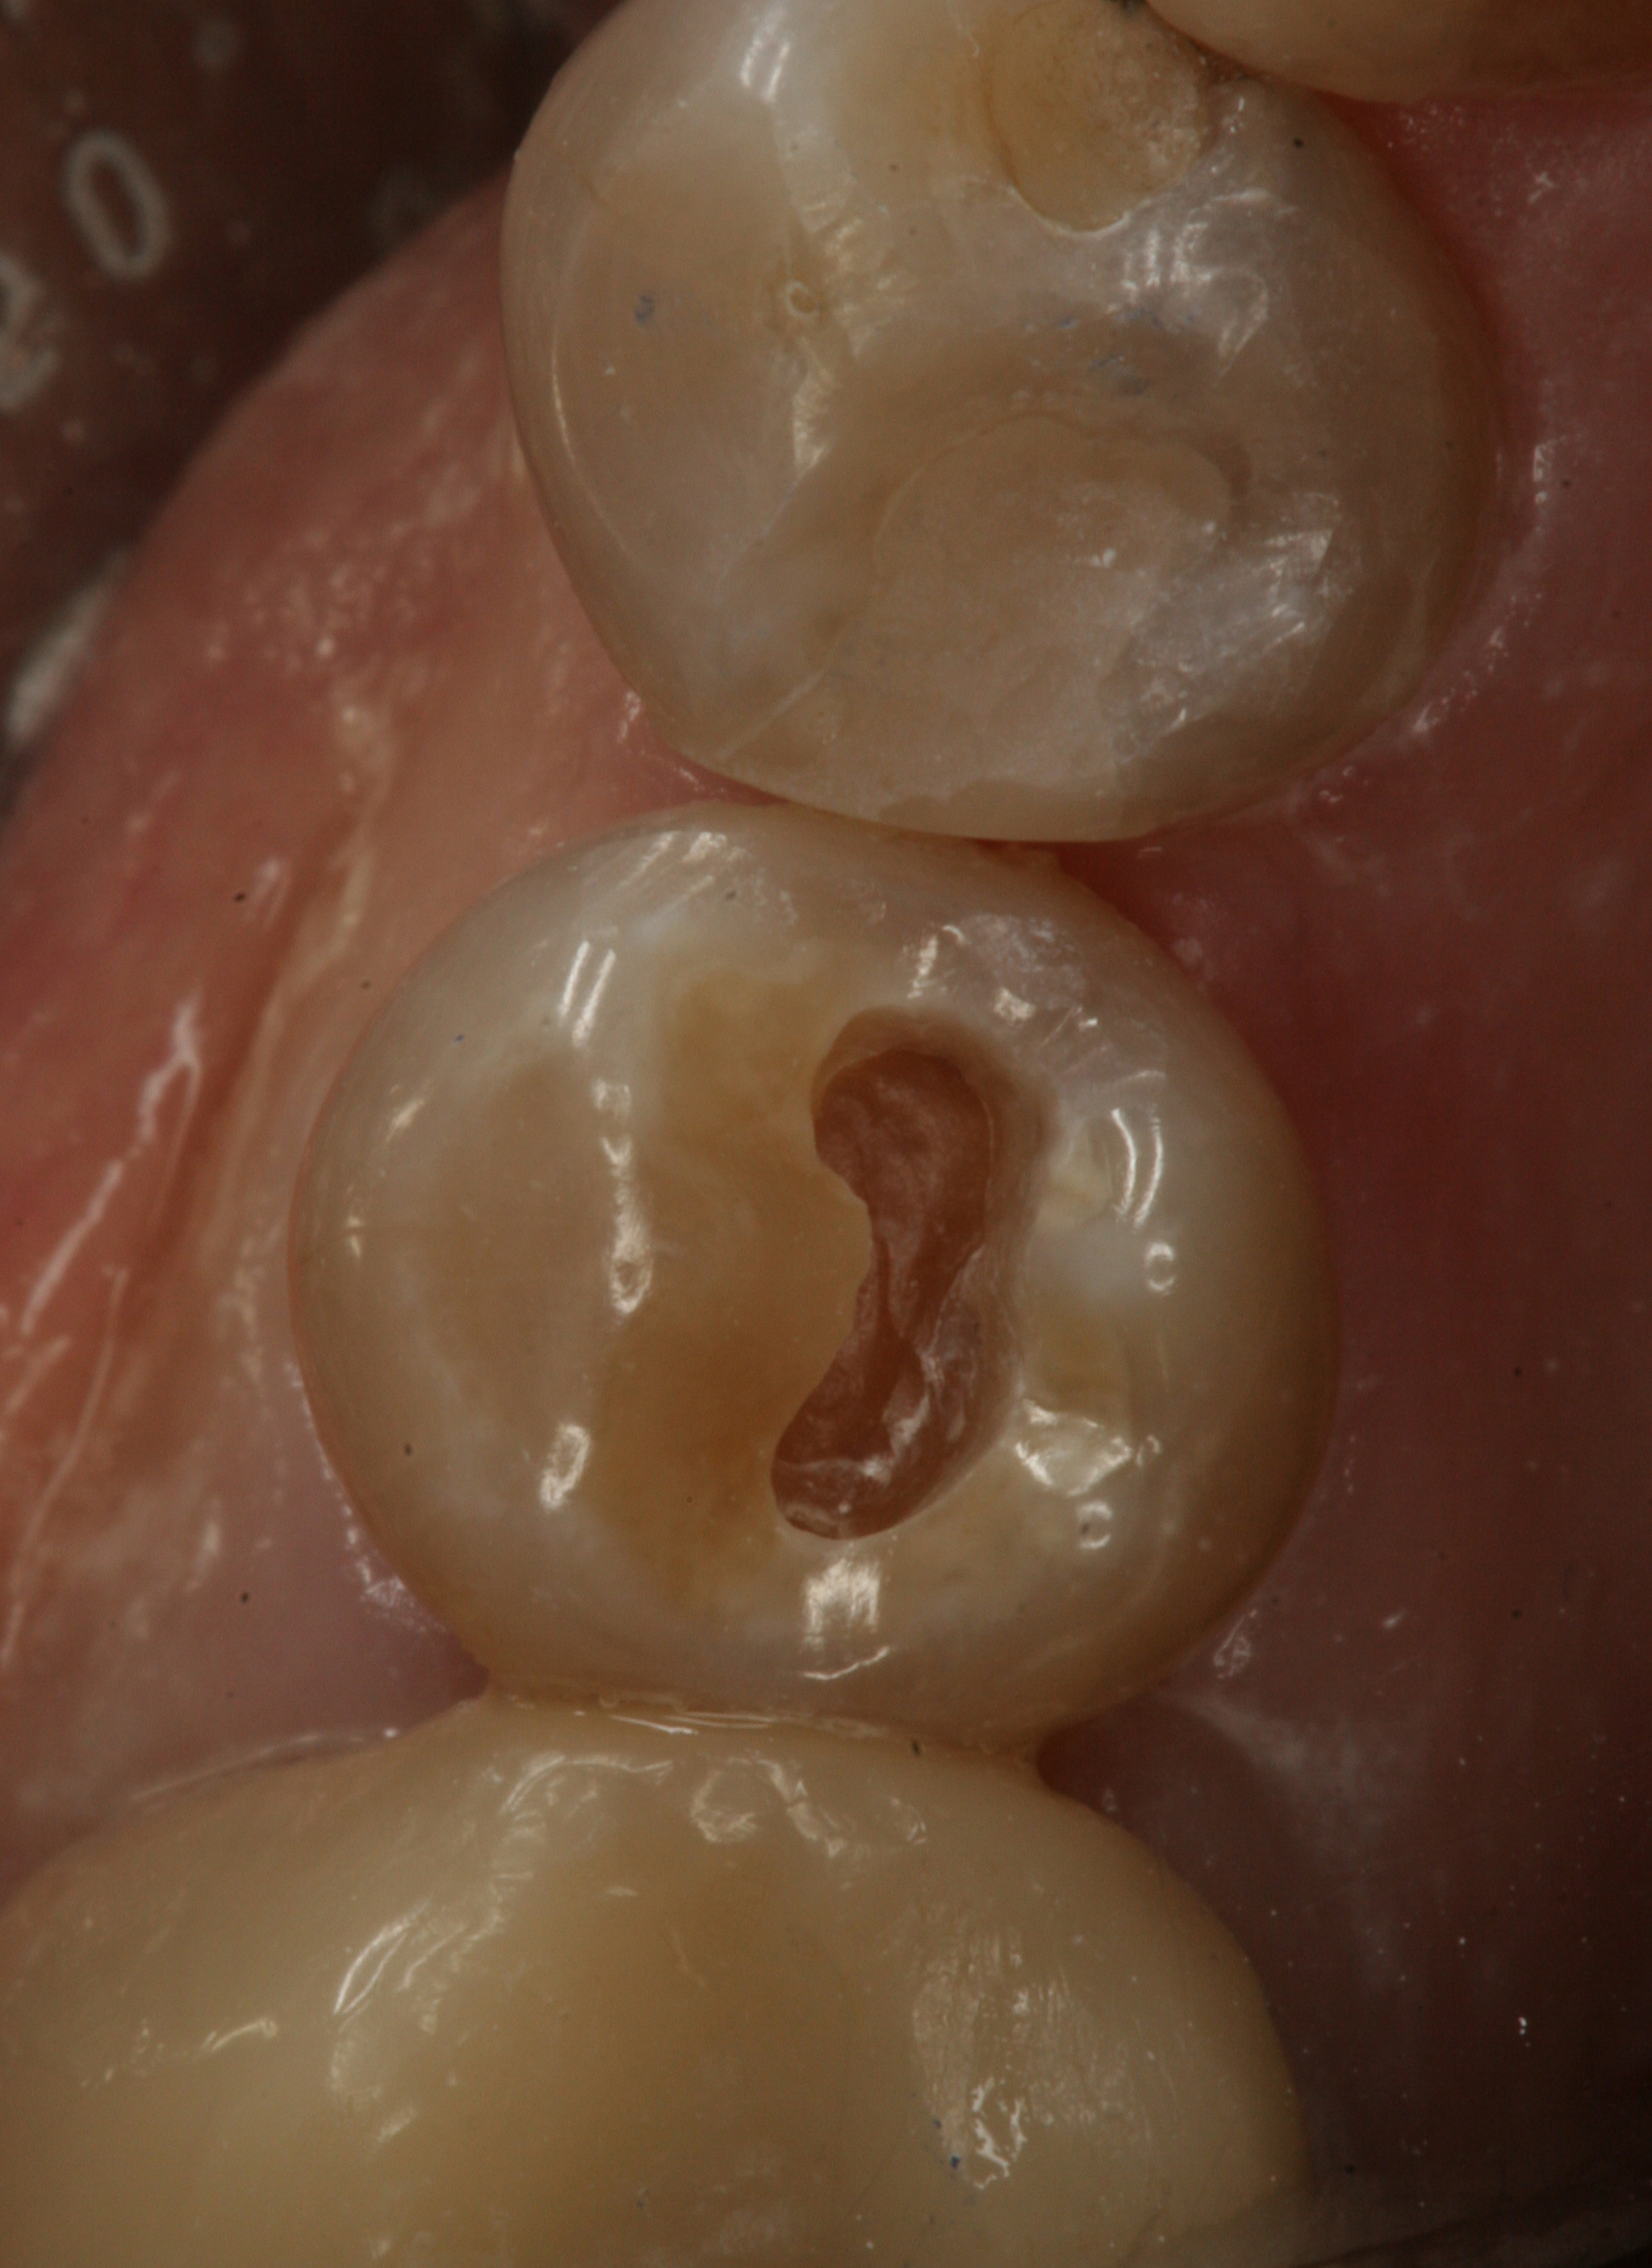

Fig 1. Preoperative view of a tetracycline-stained lower right second bicuspid.

Figure 1

Fig 2. Class I cavity preparation. Note the dark pulpal floor.

Figure 2

Fig 3. Postoperative view after placement of a smart-matching composite without the use of a stainblocker.

Figure 3

The natural color of the tooth is affected by several factors, including the tooth's position in the dental arch, whether the tooth is posterior or anterior, the age of the tooth, the amount of internal staining present, and existing restorations (Figure 1 through Figure 3).7 These factors necessitate color-matching techniques that involve a multi-layer approach using several different shades of resin composites that have been produced by pigments or dyes. A mutual color blending can occur at the restorative margin, which can be attributed to the transparent characteristics of the resin composite. However, the color blending that occurs at the margin is also dependent on the light diffusion and transmission properties of the resin composite, as well as the preparation margin configuration (Figure 2 and Figure 3), enamel prism orientation, and age of the tooth.8